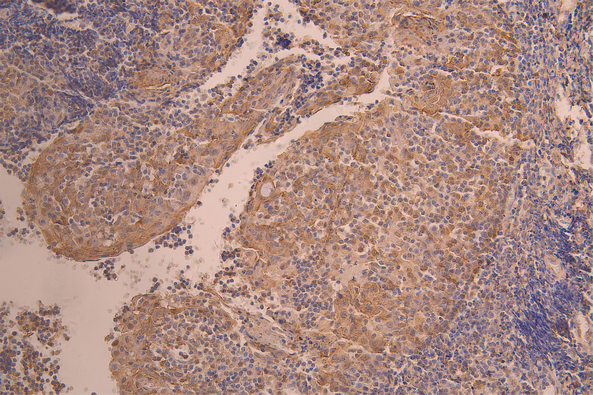

IHC image of CSB-RA011664MA3HU diluted at 1:50 and staining in paraffin-embedded human spleen tissue performed on a Leica BondTM system. After dewaxing and hydration, antigen retrieval was mediated by high pressure in a citrate buffer (pH 6.0). Section was blocked with 10% normal goat serum 30min at RT. Then primary antibody (1% BSA) was incubated at 4°C overnight. The primary is detected by a Anti-Human lgG, Fcy Fragment Specific labeled by HRP and visualized using 0.05% DAB.